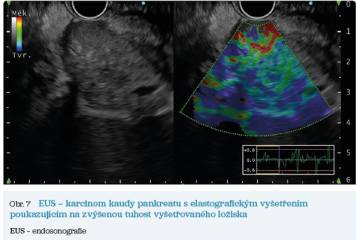

EUS umožňuje přesné vyšetření pankreatu. Lze také identifikovat a vyšetřit regionální lymfatické uzliny a vztah pankreatických lézí k okolním cévním strukturám. EUS může také sloužit jako navigace k odběru bioptického materiálu k cytologickému a histologickému vyšetření.21 AI je zde využívána k potvrzení malignity v IPMN. Kuwahara a kol. dosáhli s využitím 3 970 snímků a CNN algoritmu velké úspěšnosti v diferenciaci benigní a maligní IPMN s AUC 0,98.22 Řada studií se již zabývala AI asistovaným rozlišením chronické pankreatitidy a karcinomu pankreatu s AUC 0,940–0,986.23,24 Velká studie obsahující 1 174 461 snímků z celkem 583 případů hodnotící rozlišení autoimunitní pankreatitidy, karcinomu pankreatu, chronické pankreatitidy a normálního pankreatu dosáhla pro karcinom pankreatu AUC 0,97625 (obr. 6–9).